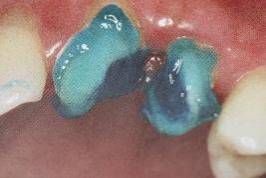

纤维桩试放时应用镊子夹持将其插入预备的根管桩道中(这涉及无菌观念和操作),就位时无阻力可稍有锢住感。

为防止裁剪过程中有可能造成桩表面的污染,可以粘结固位后再进行裁剪。

操作时,光固化灯应在树脂核成形后,颊、舌、合面分别光照20秒,在完成预备体后将其磨除。